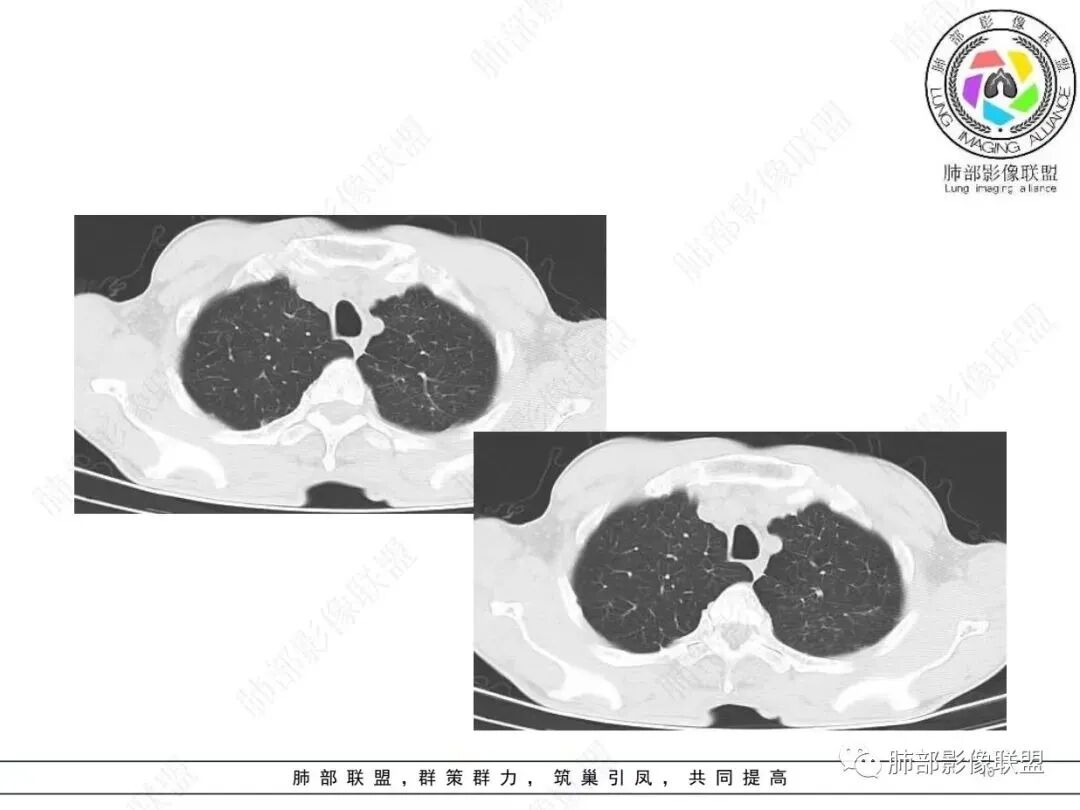

左肺及右肺中叶可见多发斑片状,条索及结节状高密度影,界不清,树芽征(+),中叶伴有支气管扩张,左肺下叶背段结节,周围伴毛刺,近端气管截断,实质密度不均匀,强化方式(看不清),8L,7及4区及左肺门见多发肿大淋巴结,老年男性,感染指标升高,呼吸道慢性病史,二元论,结核+左肺下叶背段恶性结节(鳞癌?)左肺下叶后基底段有新发感染?

左侧胸廓缩小,肺野透亮度较对侧升高,多发微小结节影,下肺结节有刀切征,周围卫星灶,长索条,胸膜增厚牵拉,周边强化,考虑结核,鉴别腺癌。

双肺上叶斑点索条影,边缘清晰,可见树芽征。右肺中叶、左肺下叶局限性支气管扩张及索条影。左肺下叶背段结节膨胀感不强,直边,不均匀强化。左侧膈肌抬高相近肺内条片状影。纵隔及左肺门淋巴结稍增大。一元:先考虑感染性病变,NTM,努卡。两元:左下肺腺癌+淋巴结转移+膈神经麻痹。

老年男性,慢性咳嗽咳痰2年,加重10 天,左肺下叶实性结节影,边缘收缩平直,支气管进入后截断,周围有树芽征及结节影,周围支气管壁增厚狭窄,右肺中叶斑片影,左肺下叶条索影,考虑肉芽肿性炎,肺结核,NTM,考虑肺结核可能性大。鉴别NTM,炎性假瘤等。

左肺下叶不规则实性结节,无毛刺,支气管进入阻塞,周围树芽,远端长索条,左侧胸膜增厚,左肺门淋巴结略增大,右肺中叶支气管扩张,考虑炎性肉芽肿,结核、NTM,鉴别腺癌

整体体积缩小,附近多发索条、斑点状高密度影,继发性结核肯定有,倾向于陈旧性,问题是:是否有继发的恶性肿瘤?薄层看看边缘是否毛刺?